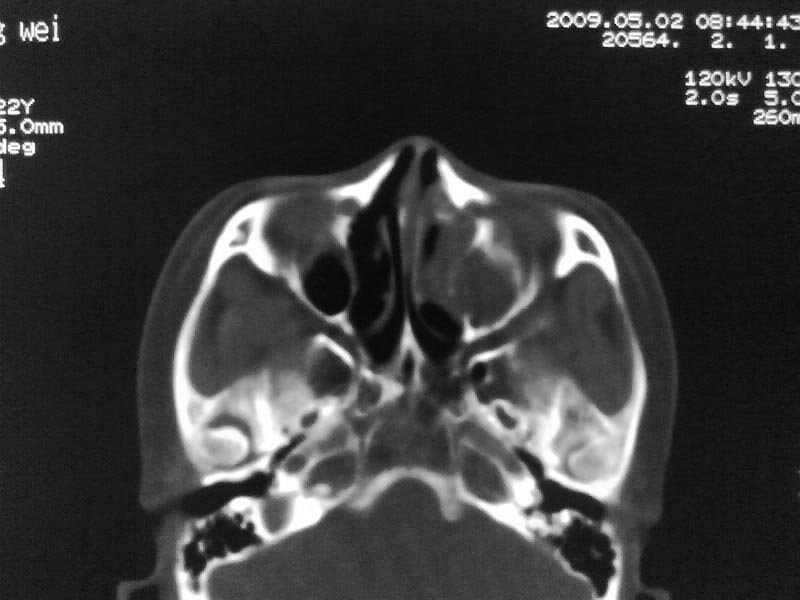

以下是引用zjzjr在2009-5-3 9:59:00的发言:[br]左侧鼻腔息肉、左侧筛窦、上颌窦炎症。双侧下鼻甲粘膜肥厚。

以下是引用随光逐影在2009-5-3 13:02:00的发言:[br]1)左侧鼻腔新生物(息肉可能)。2)左侧上颌窦及左侧筛窦炎症。3)双侧下鼻甲黏膜肥厚。